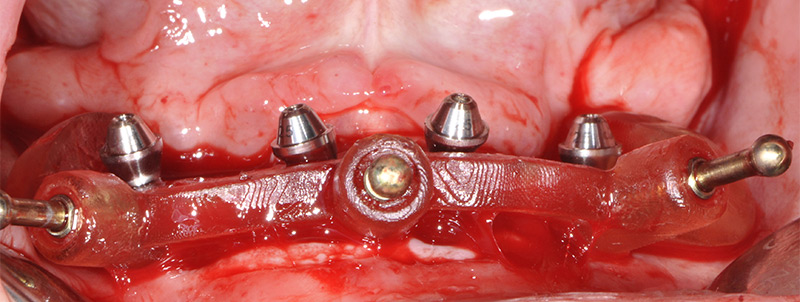

Fig. 28 : le guide de forage et d’insertion des implants est empilé sur le guide de résection laissé en place.

Fig. 29 : toujours sans toucher au guide résection, une fois les implants mis en place, les piliers prothétiques sont vissés.

Fig. 30 : enfin, la restauration transitoire est empilée sur le guide de résection pour être solidarisée en bouche aux gaines provisoires vissées sur les piliers.

Fig. 51 : les dents sont extraites sans lambeau par fractionnement puis le guide de résection osseuse est inséré et claveté dans les emplacements précédemment forés.

Fig. 52 : le guide de forage et de mise en place des implants est empilé sur le guide de résection osseuse.

Fig. 53 : vissage des piliers prothétiques dans les implants.

Fig. 54 : transvissage des gaines temporaires sur les piliers.

Les piliers prothétiques sont immédiatement vissés dans les implants sans déposer le guide de résection osseuse ; des gaines temporaires en titane sont transvissées sur les piliers et la restauration transitoire empilée sur le guide de résection, pour être solidarisée en bouche avec une colle composite. La finition très simple est réalisée au fauteuil et le patient quitte le cabinet dès la fin de la chirurgie avec sa restauration provisoire.